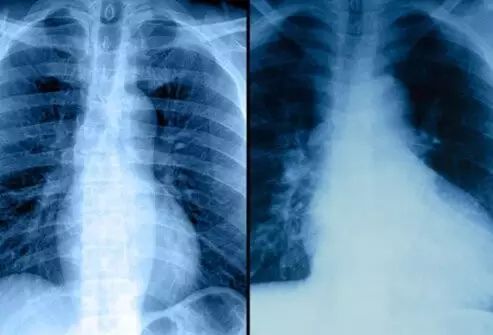

4.胸片

胸片可提供部分心脏疾病的信息,包括心脏及大血管的形态、大小、位置及波动等。心血管的常规胸片检查包括后前位、左前斜位(60°)、右前斜位(45°~50°),有时加做左侧位。

➤正位胸片能显示出心脏大血管的大小、形态、位置和轮廓,观察心脏与毗邻器官的关系和肺内血管的变化,可用于心脏及其径线的测量。

➤左前斜位片显示主动脉的全貌和左右心室及右心房增大的情况。

➤右前斜位片有助于观察左心房增大、肺动脉段突出和右心室漏斗部增大的变化。

➤左侧位片能观察心、胸的前后径和胸廓畸形等情况,对主动脉瘤与纵隔肿物的鉴别及定位尤为重要。